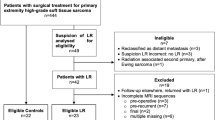

A total of 1707 postoperative follow-up MRI scans were performed in 242 patients with histologically proven STS between 2008 and 2020. Thirty-eight patients were excluded due to insufficient imaging and pathological data. Ultimately, 204 patients with a total of 1286 postoperative follow-up MRI scans were included in our study and presented complete data on imaging. Examinations in which predictive values could not be determined and the last examination of each patient were excluded (n = 231; Fig. 1). Either core needle or open biopsy was performed in all lesions suspected of being recurrences (n = 88). In these patients, the pathological reports were set as reference and the radiological findings were correlated to the pathological reports. All other MRIs were reviewed during the subsequent MRI follow-up examinations, showing whether lesions had been overlooked in the previous MRIs. These subsequent MRI follow-ups took place after 3 to 6 months. The follow-up MRIs were reviewed by two dedicated musculoskeletal radiologists with a minimum of 5 years of experience in sarcoma diagnostics, with findings reached by consensus. The reports were divided into two groups: presence of recurrence and absence of recurrence. From these findings we extracted true-positive/−negative and false-positive/−negative MRI findings in detecting recurrent STS. The false-negative results were derived retrospectively by reviewing the subsequent MRI follow-ups. Latest recurrences were clearly delimited after two such follow-ups.

The median age of the patients was 55.3 years (Min.: 10, Max.: 88, SD: 18.2). Of the patients, 52.9% were male (n = 108; Table 1). The overall median recurrence-free follow-up interval on MRI was 39 months (Min.: 3, Max.: 161). No significant difference was observed in the median recurrence-free follow-up intervals in a comparison of patients after surgery alone (37 months) and surgery with additional radiation therapy (35 months), or in subcutaneous (37 months) and intramuscular lesions (36 months). In all, 34.8% of the patients presented with recurrences. Sixty-five follow-up MRI scans were diagnosed as true positive, 23 as false positive, 6 as false negative, and 961 as true negative (Table 2 and Fig. 2). Overall, sensitivity and specificity of MRI for detecting recurrences were 92% and 98%, respectively, with an accuracy of 97%. For intramuscular lesions the sensitivity was higher than for subcutaneous lesions (95% and 83%, respectively), at similarly high specificities (97% and 98%, respectively; Tables 3 and 4). Furthermore, the sensitivity was higher in patients after surgery alone than after surgery with additional radiation therapy (97% and 86%, respectively), at similar specificities (96% and 98%, respectively; Tables 3 and 5). The 6 false-negative results were found in streaky (n = 2) and small ovoid/nodular (n = 4) recurrences. The false-positive lesions imitated streaky (n = 14), ovoid/nodular (n = 8; Fig. 3), and polycyclic/multilobulated recurring lesions (n = 1). All false-positive results were found in patients in whom the primary STS was polycyclic/multilobulated in appearance. Furthermore, 22 of the 23 false-positive results were derived from patients with R0 resection (95.7%). Altogether, 92.2% of the patients underwent R0 resection.